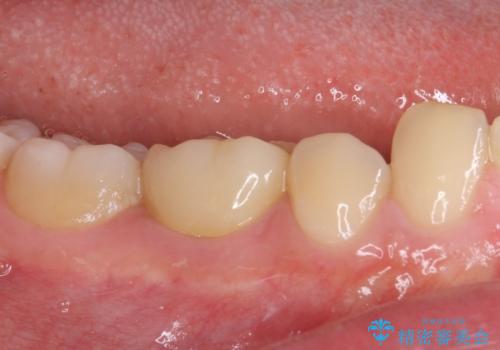

虫歯除去後に痛みは収まり、神経も保存することができました。

変色していた歯もセラミッククラウンで自然な色合いとなり、患者様には大変満足していただきました。